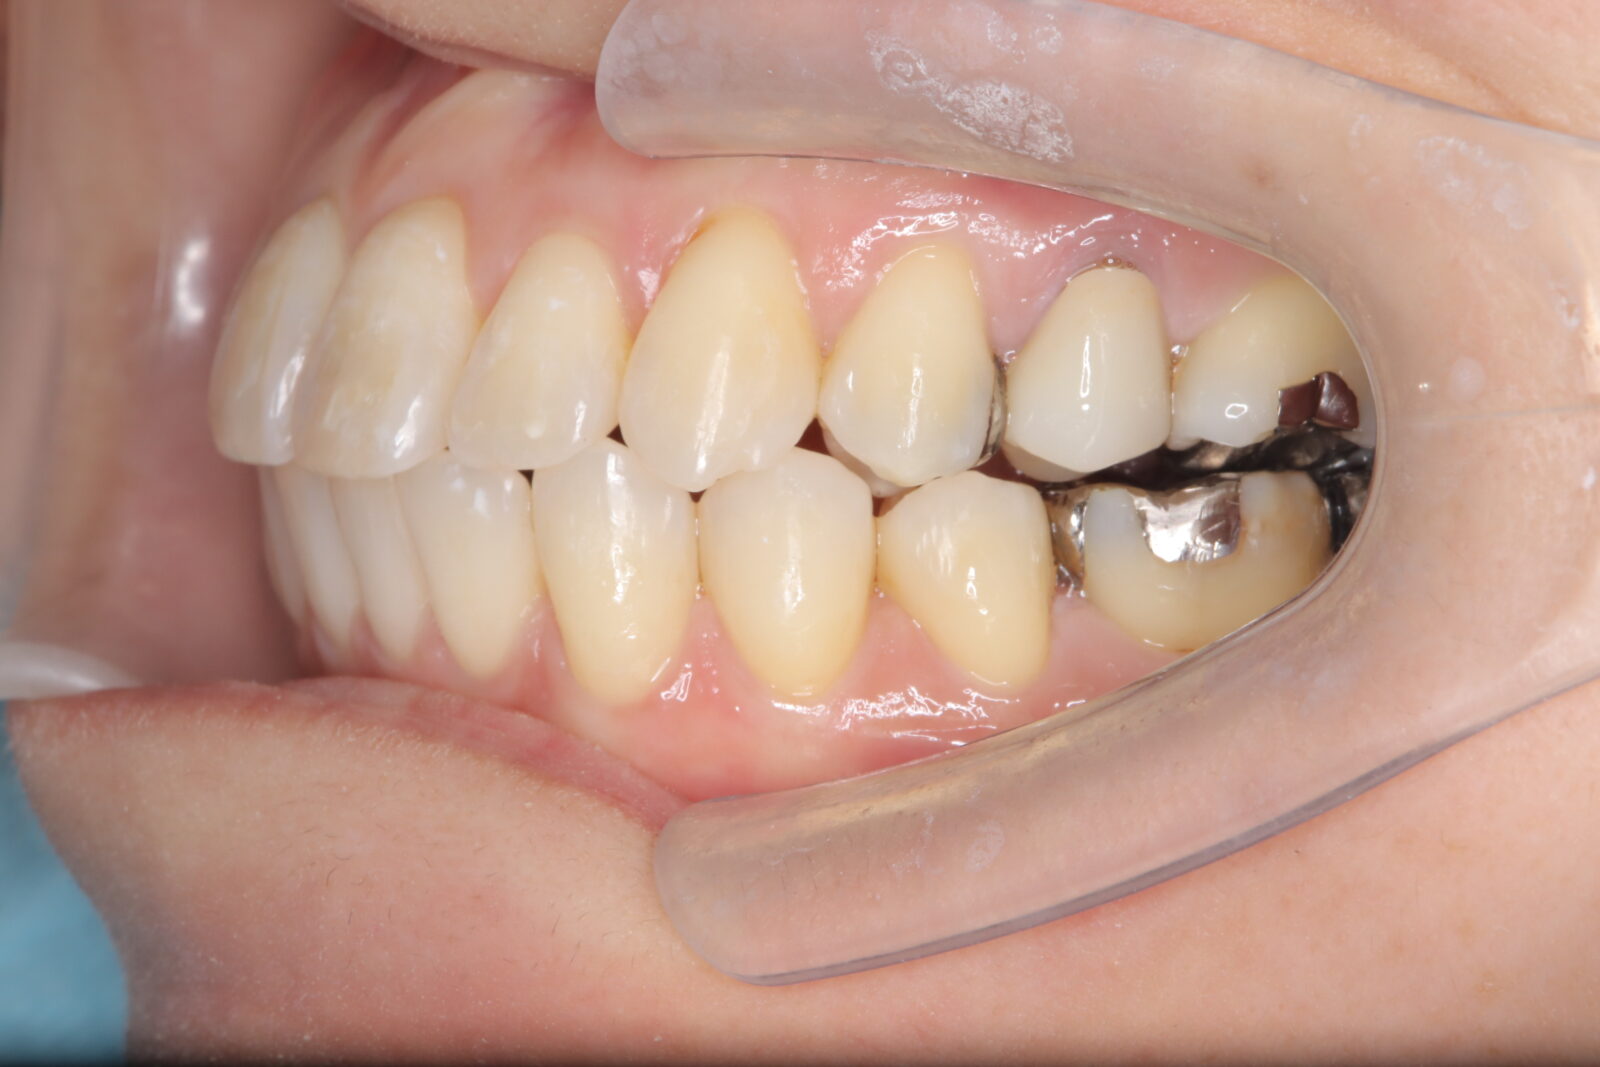

デンチャー+補綴+マウスピース矯正の症例

左上4〜7番に虫歯。右の親知らずの歯周ポケットは10mmあったため抜歯した。

左上6番の遠心は虫歯の範囲が大きすぎたため抜歯。義歯の安定を考慮すると、左上臼歯部をブリッジにするよりも、両側に義歯の人工歯を配置する方が良いと判断した。

本人の希望で薄く、口蓋を覆わない設計とした。

下顎前歯は抜歯後の治癒待ち、左上の虫歯治療中にインビザラインで歯列を整えた。

義歯作成期間中も歯の移動を行い、最終的には、計画通りに上顎の新義歯装着と同時に下顎のリテーナーを装着できた。

スマイルデンチャー

ジルコニアクラウン

インビザライン

治療期間約5ヶ月